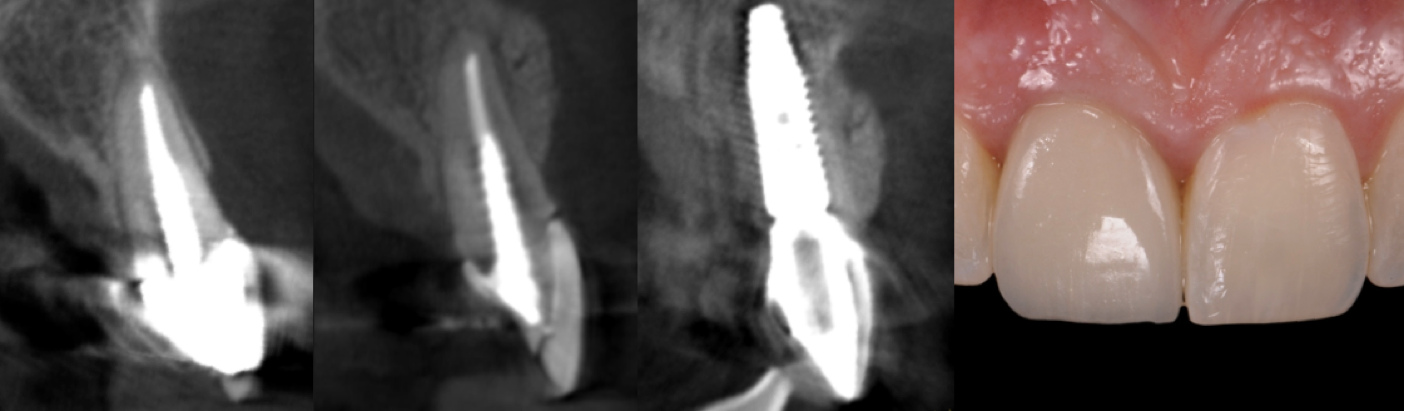

Patient with congenitally missing lateral incisors. The S.M.A.R.T. minimally invasive bone grafting technique provides predictable horizontal bone augmentation with fewer complications, less pain and swelling. S.M.A.R.T. bone graft was performed on both lateral incisor sites using a single incision.

The S.M.A.R.T. approach facilitates flapless implant placement, which may be followed by delivery of a temporary restoration. This results in fewer procedures compared to traditional techniques. Treatment duration is decreased, with less discomfort and less expense to the patient, while preserving soft tissue architecture.

S.M.A.R.T. bone graft helps to enhance the esthetic appearance of implant restorations. The presence of sufficient bone volume makes ideal implant placement possible, facilitating natural restorative contours and emergence profiles.